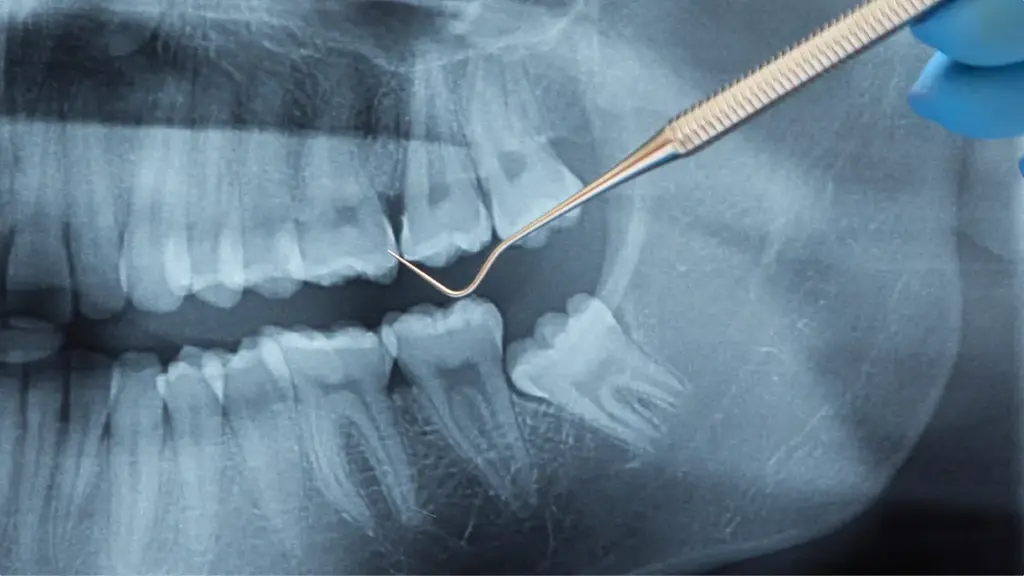

親知らずの抜歯は、歯が生えている位置や向き、上あごか下あごかといった条件によって、治療の難易度が大きく異なります。すでに歯の頭が歯ぐきの外に出ている親知らずや、上あごに生えている親知らずの場合は、比較的スムーズに抜歯できるケースが多く、処置時間や身体への負担も抑えられることが一般的です。一方で、下あごの骨の中に横向きや斜めに埋まっている親知らずは、神経や血管との位置関係も考慮する必要があり、難易度の高い治療となります。

そのような場合には、歯ぐきを切開して親知らずを露出させ、タービンと呼ばれる専用の機械を用いて歯を分割し、少しずつ取り出していきます。状態によっては、歯だけでなく周囲のあごの骨を一部削る必要が生じることもありますが、周囲組織への影響を最小限に抑えながら、慎重に処置を進めていきます。事前にレントゲンや必要な検査を行い、歯の状態を正確に把握したうえで、安全性を重視した治療計画を立てます。